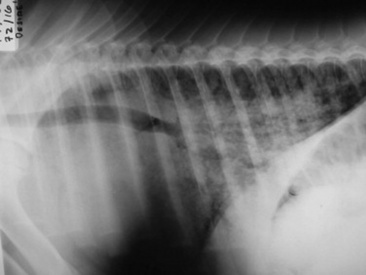

Fungal pneumonia may be diagnosed from samples obtained by tracheal wash or BAL or via a lung biopsy (Fig. 31-17). Lung biopsy is associated with significant risk if a pulmonary vessel is accidentally biopsied. The biopsy should be performed ideally after radiographic evaluation or with concurrent ultrasound guidance, and the sample should be obtained from the periphery of the lung; however, some horses have experienced fatal hemorrhage associated with biopsy of a vessel only 2 cm from the periphery. The lung is rich in plasminogen, so bleeding complications may be severe. Spring-loaded biopsy needles are safer for lung biopsy than Tru-Cut biopsy instruments.324 Ultrasound evaluation can be used to monitor for bleeding after the procedure.

image

Fig. 31-17 Percutaneous lung biopsy from caudal periphery of lung of a weanling foal.